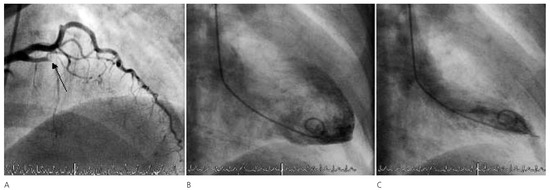

Six Simultaneously Employed Methods to Gauge the Coronary Collateral Flow of the Decade

by Steffen Gloekler, Tobias Rutz and Christian Seiler

Cardiovasc. Med. 2007, 10(9), 298; https://doi.org/10.4414/cvm.2007.01264 - 28 Sep 2007

Viewed by 57

Abstract

Case report. A 59-year-old woman with bronchial asthma and obesity underwent coronary angiography because of exertional dyspnea and atypical chest pain both at rest and sometimes during exertion[...] Full article

Show Figures

Figure 1